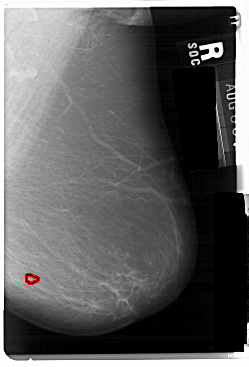

A_1111_1.RIGHT_MLO

RIGHT_MLO LINES 5491 PIXELS_PER_LINE 3721 BITS_PER_PIXEL 12 RESOLUTION 43.5 OVERLAY

FILE: A_1111_1.RIGHT_MLO.OVERLAY

TOTAL_ABNORMALITIES 1

ABNORMALITY 1

LESION_TYPE MASS SHAPE ROUND MARGINS ILL_DEFINED

ASSESSMENT 4

SUBTLETY 3

PATHOLOGY MALIGNANT

TOTAL_OUTLINES 1

BOUNDARY